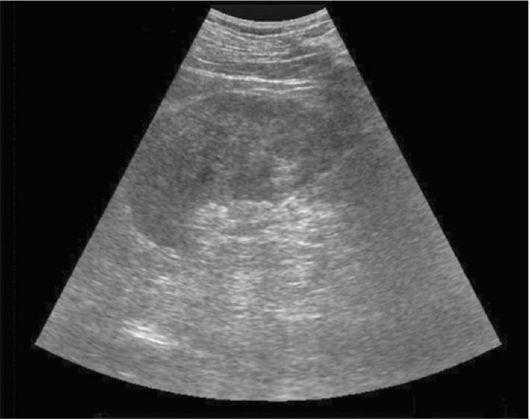

Π ΠΈΡ. 7.3. Π‘ΠΎΠ½ΠΎΠ³ΡΠ°ΠΌΠΌΠ° Π»Π΅Π²ΠΎΠΉ ΠΏΠΎΡΠΊΠΈ. ΠΡΡΡΡΠΉ Π³Π½ΠΎΠΉΠ½ΡΠΉ ΠΏΠΈΠ΅Π»ΠΎΠ½Π΅ΡΡΠΈΡ. Π ΠΏΠ°ΡΠ΅Π½Ρ ΠΈΠΌΠ΅ ΠΏΠΎΡΠΊΠΈ ΠΎΠΏΡΠ΅Π΄Π΅Π»ΡΠ΅ΡΡΡ ΡΡΠ°ΡΡΠΎΠΊ Ρ Π½Π΅ΠΎΠ΄Π½ΠΎΡΠΎΠ΄Π½ΠΎΠΉ ΡΡ ΠΎΡΡΡΡΠΊΡΡΡΠΎΠΉ

Π Π½Π°ΡΡΠΎΡΡΠ΅Π΅ Π²ΡΠ΅ΠΌΡ ΡΡΠ΅Π΄ΠΈ ΠΌΠ΅ΡΠΎΠ΄ΠΎΠ² Π΄ΠΈΠ°Π³Π½ΠΎΡΡΠΈΠΊΠΈ ΠΎΡΡΡΠΎΠ³ΠΎ ΠΏΠΈΠ΅Π»ΠΎΠ½Π΅ΡΡΠΈΡΠ° Π²Π°ΠΆΠ½ΠΎΠ΅ ΠΌΠ΅ΡΡΠΎ Π·Π°Π½ΠΈΠΌΠ°Π΅Ρ ΡΠ»ΡΡΡΠ°Π·Π²ΡΠΊΠΎΠ²ΠΎΠ΅ ΡΠΊΠ°Π½ΠΈΡΠΎΠ²Π°Π½ΠΈΠ΅ ΠΏΠΎΡΠ΅ΠΊ, ΠΎΡΠΎΠ±Π΅Π½Π½ΠΎ ΠΏΡΠΈ II ΡΡΠ°Π΄ΠΈΠΈ ΡΠ°Π·Π²ΠΈΡΠΈΡ Π²ΠΎΡΠΏΠ°Π»ΠΈΡΠ΅Π»ΡΠ½ΠΎΠ³ΠΎ ΠΏΡΠΎΡΠ΅ΡΡΠ°. ΠΠΎ ΠΌΠ΅ΡΠ΅ ΡΠ°Π·Π²ΠΈΡΠΈΡ Π²ΠΎΡΠΏΠ°Π»Π΅Π½ΠΈΡ ΠΈ Π½Π°ΡΠ°ΡΡΠ°Π½ΠΈΡ ΠΎΡΠ΅ΠΊΠ° ΠΏΠΎΡΠ΅ΡΠ½ΠΎΠΉ ΡΠΊΠ°Π½ΠΈ ΡΡ ΠΎΠ³Π΅Π½Π½ΠΎΡΡΡ ΠΏΠ°ΡΠ΅Π½Ρ ΠΈΠΌΡ ΠΏΠΎΡΠΊΠΈ ΡΠ²Π΅Π»ΠΈΡΠΈΠ²Π°Π΅ΡΡΡ ΠΈ Π»ΡΡΡΠ΅ Π΄ΠΈΡΡΠ΅ΡΠ΅Π½ΡΠΈΡΡΠ΅ΡΡΡ Π΅Π΅ ΠΊΠΎΡΠΊΠΎΠ²ΡΠΉ ΡΠ»ΠΎΠΉ ΠΈ ΠΏΠΈΡΠ°ΠΌΠΈΠ΄Ρ, Π° ΡΠ°ΠΊΠΆΠ΅ ΠΎΡΠΌΠ΅ΡΠ°Π΅ΡΡΡ ΠΎΠ³ΡΠ°Π½ΠΈΡΠ΅Π½ΠΈΠ΅ ΠΏΠΎΠ΄Π²ΠΈΠΆΠ½ΠΎΡΡΠΈ ΠΏΠΎΡΠΊΠΈ ΠΏΡΠΈ Π΄ΡΡ Π°Π½ΠΈΠΈ. ΠΠ»Ρ ΠΊΠ°ΡΠ±ΡΠ½ΠΊΡΠ»Π° ΠΏΠΎΡΠΊΠΈ Ρ Π°ΡΠ°ΠΊΡΠ΅ΡΠ½Ρ Π²ΡΠ±ΡΡ Π°Π½ΠΈΠ΅ Π΅Π΅ Π²Π½Π΅ΡΠ½Π΅Π³ΠΎ ΠΊΠΎΠ½ΡΡΡΠ° ΠΈ ΠΎΡΡΡΡΡΡΠ²ΠΈΠ΅ Π΄ΠΈΡΡΠ΅ΡΠ΅Π½ΡΠΈΠ°ΡΠΈΠΈ ΠΌΠ΅ΠΆΠ΄Ρ ΠΊΠΎΡΠΊΠΎΠ²ΡΠΌ ΠΈ ΠΌΠΎΠ·Π³ΠΎΠ²ΡΠΌ ΡΠ»ΠΎΡΠΌΠΈ. ΠΡΠΈ ΡΠΎΡΠΌΠΈΡΠΎΠ²Π°Π½ΠΈΠΈ Π°Π±ΡΡΠ΅ΡΡΠ° Π² Π΅Π³ΠΎ ΡΠ΅Π½ΡΡΠ΅ Π²ΠΈΠ΄Π½Ρ Π³ΠΈΠΏΠΎΡΡ ΠΎΠ³Π΅Π½Π½ΡΠ΅ ΡΡΡΡΠΊΡΡΡΡ (ΡΠΈΡ. 7.3). ΠΡΠΈ Π²ΡΠΎΡΠΈΡΠ½ΠΎΠΌ ΠΎΡΡΡΠΎΠΌ ΠΏΠΈΠ΅Π»ΠΎΠ½Π΅ΡΡΠΈΡΠ΅ ΠΌΠΎΠΆΠ½ΠΎ Π²ΡΡΠ²ΠΈΡΡ ΠΈΠ·ΠΌΠ΅Π½Π΅Π½ΠΈΡ, Ρ Π°ΡΠ°ΠΊΡΠ΅ΡΠ½ΡΠ΅ Π΄Π»Ρ ΠΏΠ΅ΡΠ²ΠΈΡΠ½ΠΎΠ³ΠΎ Π·Π°Π±ΠΎΠ»Π΅Π²Π°Π½ΠΈΡ ΠΏΠΎΡΠΊΠΈ.